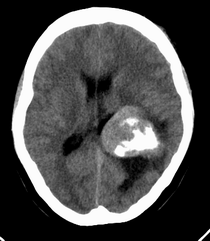

患者,女性,33岁,外伤检查发现,既往没有明显类似病史。

ct平扫见左侧脑室后角不规则形,边界不清的等密度肿块,肿瘤内有钙化,瘤周可见残存的脑室(低密度脑脊液影),考虑脉络脉丛乳头状瘤或室管膜瘤.

左侧侧脑室三角区占位性病变,其特点是平扫边界清、密度高、其内可见大块结节样的钙化,首先考虑起源于侧脑室三角区残余蛛网膜上皮的脑膜瘤可能性最大,无论是形态、密度、好发部位均符合脑膜瘤特点,建议增强进一步检查。

左侧脑室内软组织肿物,内部见多发不规则钙化,边界清楚锐利,有分叶。相应左侧脑室扩张。常见的不外乎3种病:室管膜瘤,脑膜瘤,脉络脉丛乳头状瘤。脑膜瘤分叶较少见,脉络脉丛乳头状瘤钙化较少见,因此,室管膜瘤可能性最大。

1室管膜瘤(肿瘤以膨胀性生长,有包膜,与周围分界清晰,大多位于脑室内ct表现为等密度,稍高密度肿快,边缘不光整呈分爷状。瘤内常见小圆状,块状钙化影。)2脑室内脑膜瘤(多位于侧脑室三角区ct平扫表现稍高于脑组织的肿快,无明显钙化。好发成年女性。)3脉络丛乳头状瘤(易引起交通性脑积水,颅高压症状明显)。总和以上考虑室管膜瘤可能性大。

左侧脑室内见不规则略高密度团块影,边缘分叶,内见多发不规则钙化,病灶与侧脑室壁关系较为密切,左侧脑室扩大。考虑室管膜瘤可能性较大,其次为脑膜瘤,脉络丛乳头状瘤的可能性最小。

患者,女性,33岁,外伤检查发现,既往没有明显类似病史;

1、病灶除钙化外其它部分质均匀,无明显密度差别;

2、病灶界清,呈现膨胀性生长,对周围组织无明显浸润表现;

3、钙化部分范围较大,呈现大片状钙化;

4、病人为成年女性,无明显不适;

考虑:脑膜瘤;

鉴别诊断:室管膜瘤;脉络膜乳头状瘤;

平扫见左侧脑室三角区不规则形肿块,肿瘤内有钙化,瘤周可见残存的脑室(低密度脑脊液影),考虑脉络脉丛乳头状瘤或室管膜瘤.

侧脑室三角区占位,首先考虑脑膜瘤,其次考虑室管膜瘤,室管膜瘤相对密度混杂一些,低一些。脉络丛乳头状瘤可能性不大,因为没有脑脊液明显增多改变,而且成人多在四脑室。

因病人无交通性脑积水,故脉络丛乳头状瘤不支持,脑室内脑膜瘤及室管膜瘤均有可能,病灶密度较高,前者可能性更大,建议结合增强检查。